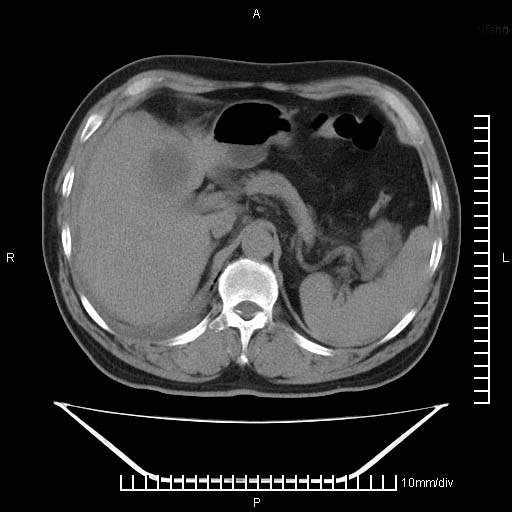

标题: CT25082:肝脏增强:男性,70岁 [打印本页]

标题: CT25082:肝脏增强:男性,70岁

患者以心脏疾病收住院,腹部无明显症状,b超查肝脏有占位。

增强效果不理想。考虑转移,胆囊壁明显增厚,不排除胆囊癌肝转移。

病灶无强化,考虑囊肿。

牛眼征,中心坏死无强化,外缘强化,最外缘又见低密度,考虑转移,与脓肿鉴别

肝内多发转移瘤,右下肺炎症并少量胸水。胃壁增厚建议胃镜,胰尾部“病变”为肠管。

1)肝脏多发性转移瘤(不排除胰尾癌转移所致可能)。2)腹水。3)右侧少量胸腔积液。

ct25082 结果:转移瘤

外院mr结果:胰尾恶性占位。